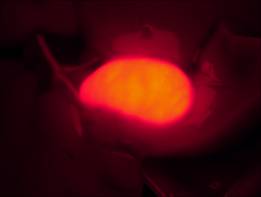

[客戶實驗方法] 以小白鼠作為實驗動物模型,通過體視熒光顯微鏡觀察實驗組和對照組,在同一參數(shù)設置下,用明美成像系統(tǒng)分析軟件將明場、熒光分別拍攝的效果圖合成,檢測藥物作用部位。

藥物膽熒光